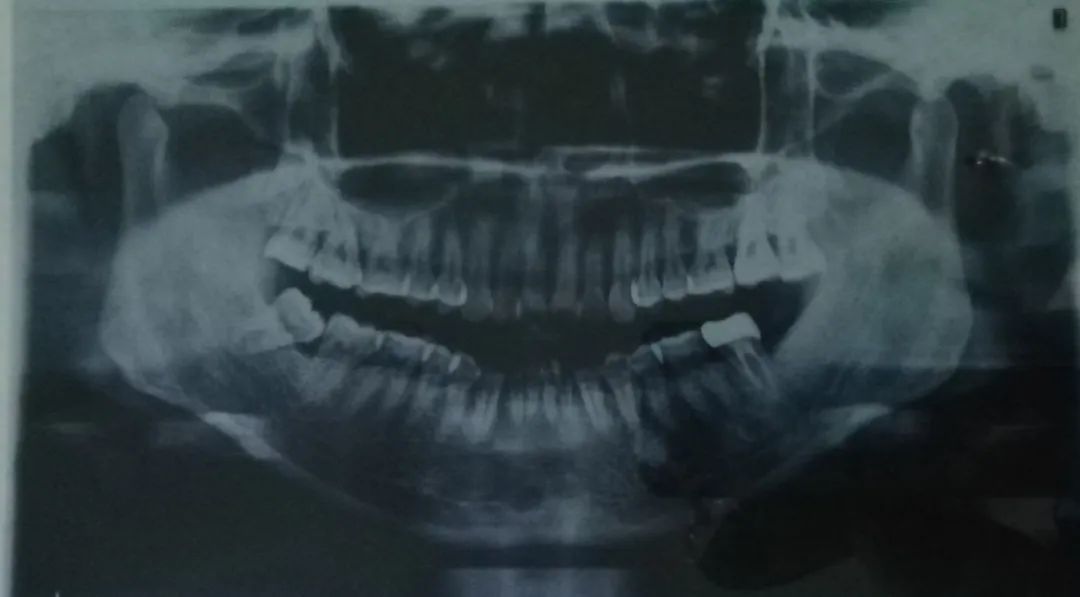

比如ct片、牙片,可以清晰的看出牙齒的問題

我拍出的片子……真是一言難盡

我不惜獻(xiàn)丑讓大家看我的牙片,正面看主要是中間牙齒的排列不齊,但從側(cè)面看簡直驚人,以前覺得我的凸嘴可能就是骨性問題,也不覺得上牙齒有多難看,看牙片就會發(fā)現(xiàn)這齙牙齙的也太離譜,不整都對不起自己。